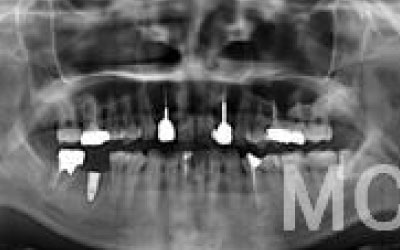

CTでは、骨や歯の状態を3Dで確認でき、正確な距離の測定も行えます。

骨の厚さや傾き、神経の位置などを事前にしっかりと測定することで、安全にインプラントを行うことができます。